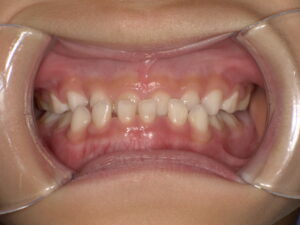

下の歯の前歯が上の歯の前歯に覆い被さっていて、下の歯の前歯がいちばん前にある状態は『反対咬合』と言われる不正咬合の一種です。就学前の小さなお子様がこの状態になる原因は、何らかのクセやきっかけ、習慣などで上下のかぶさりが逆になったことが始まりのことが多いです。遺伝的な要因がない場合、プレオルソという矯正装置を就寝時に使用して治療することで改善します。お子様が、このお写真のような歯並びになっている方はぜひ一度ご相談ください。